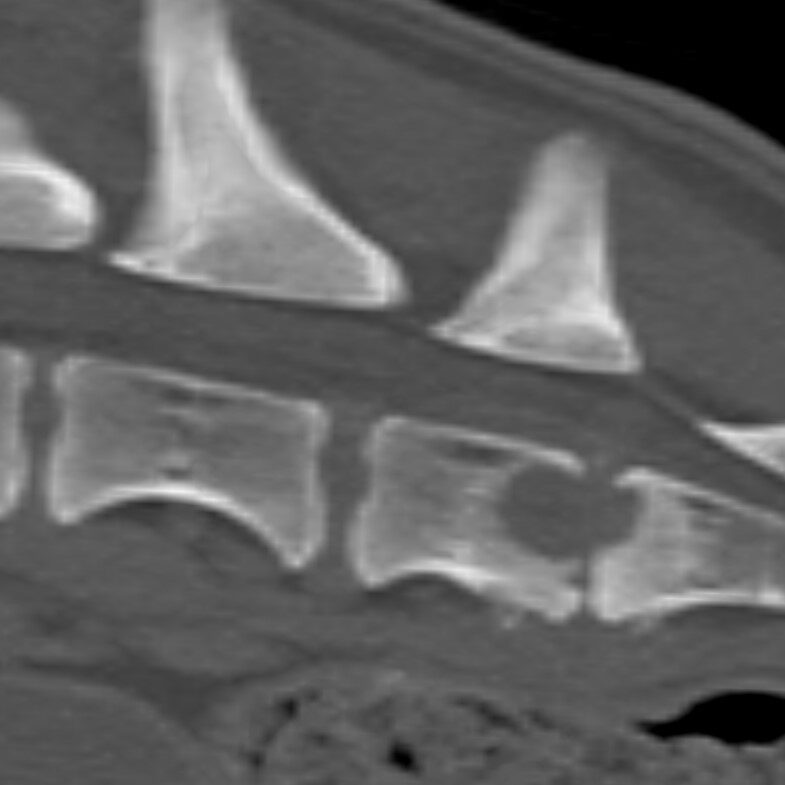

A radiograph of the spine will typically reveal damage to the vertebrae adjacent to the affected disc. The spine can become deformed and undergo bone changes as a result of chronic conditions. Radiographs may not show changes for 3-6 weeks after clinical signs begin, so if the first radiographs are normal, but the clinical signs are progressing, it is sensible to repeat them some time later.

When a typical lesion is detected, radiographs of the entire spine are recommended since some pets have multiple lesions. When a disc is infected, it degenerates and destroys the ends of adjacent vertebrae. There is evidence that these degenerative changes may weaken the vertebral column and make it more susceptible to pathologic fractures, which are caused by infection rather than trauma. As part of the healing process, the body may attempt to bridge the damaged area with bone, which may encroach on the spinal cord and nerve roots, resulting in further complications.

Imaging techniques such as computed tomography (CT) and magnetic resonance imaging (MRI) are more sensitive than plain radiography, particularly when it comes to detecting the problem early on.